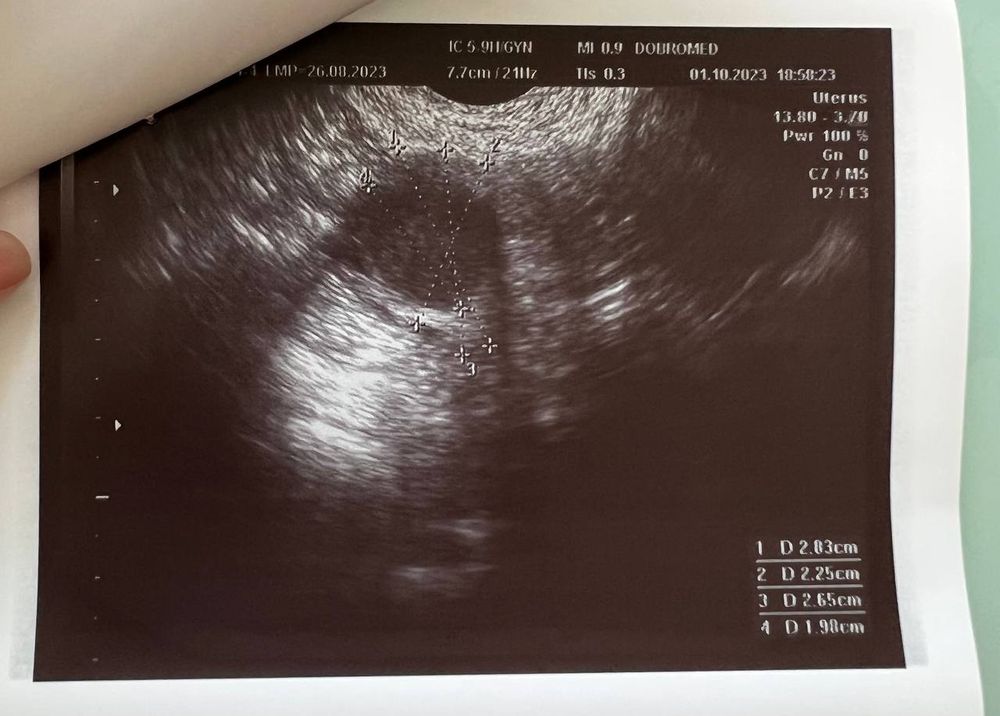

Вчера (1 октября) сходила на УЗИ, беременность подтвердили, маточная.

Размер плодного яйца 4 мм.

Но не видно желтое тело, и мутное содержимое плодного яйца (как она сказала). Меня напугала очень узистка... мол, может быть замершая беременность.

Если есть специалисты тут - пожалуйста, посмотрите снимок

Ниже фото заключения и УЗИ: